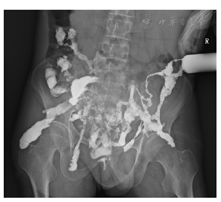

入院后查体:体温39 ℃,消瘦(体重指数16.65 kg/m2),中下腹轻压痛,腰骶部可见3处皮肤瘘口伴脓性分泌物。血白细胞计数8.51×109/L,中性粒细胞比例84.2%,血红蛋白69 g/L,血小板计数335×109/L。白蛋白24 g/L,红细胞沉降率87 mm/h,C反应蛋白120 mg/dl。腰骶部脓性分泌物培养结果示肺炎克雷伯菌、光滑假丝酵母菌阳性。结肠镜进镜至距肛缘约60 cm见结肠内瘘口,局部肉芽组织增生,降结肠及脾曲见另两处瘘口形成(图1)。窦道造影可见水溶性造影剂经皮进入窦道,中下腹部多发窦道显影,与小肠、横结肠相通(图2)。小肠CT示克罗恩病术后改变,空肠、盆组回肠克罗恩病活动期改变伴小肠-结肠管内瘘形成,病变肠管与双侧髂肌、右侧闭孔内肌、骶前区多发瘘管形成;骶骨周围、左侧坐骨直肠窝蜂窝织炎及脓肿;双侧臀大肌多发脓肿;右侧输尿管下段与病变肠管粘连,右侧输尿管积水(图3)。磁共振尿路造影示右侧输尿管下段狭窄伴右肾及输尿管中上段扩张积水(图4)。